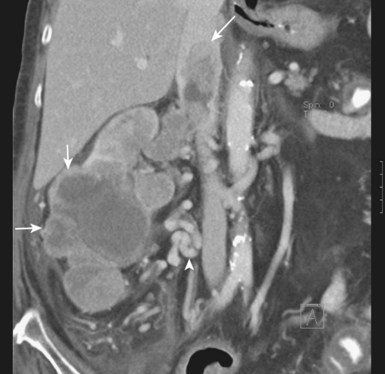

MRI is a noninvasive and accurate modality for demonstrating both the presence and the cephalad extent of vena caval involvement and has been the preferred diagnostic study at most centers for the past few decades (Goldfarb et al, 1990; Kallman et al, 1992; Bechtod and Zagoria, 1997; Choyke, 1997; Oto et al, 1998; Sun et al, 1999). Administration of gadolinium during the study often allows tumor thrombi to be differentiated from bland thrombus, because the latter does not demonstrate enhancement. More recent evidence suggests that multiplanar CT can provide essentially equivalent information, including delineation of the cephalad and caudal extent of the thrombus (Fig. 49–26) (Pretorius et al, 2000; Choyke et al, 2001; Bassignani, 2006; Zhang et al, 2007a; Bach and Zhang, 2008; Ng et al, 2008; Herts, 2009). The importance of high-quality preoperative imaging cannot be overemphasized and should be obtained as close as possible to the date of surgery because progression of the tumor thrombus may mandate important changes in intraoperative management (Blute et al, 2004b; Wotkowicz et al, 2008).

Figure 49–26 CT scan demonstrating lower pole right renal cell carcinoma (small arrows) with level III inferior vena cava (IVC) thrombus. The large arrow indicates the upper extent of the tumor thrombus within the intrahepatic portion of the IVC. The arrowhead indicates extensive retroperitoneal venous collateral vessels associated with restricted flow within the IVC.